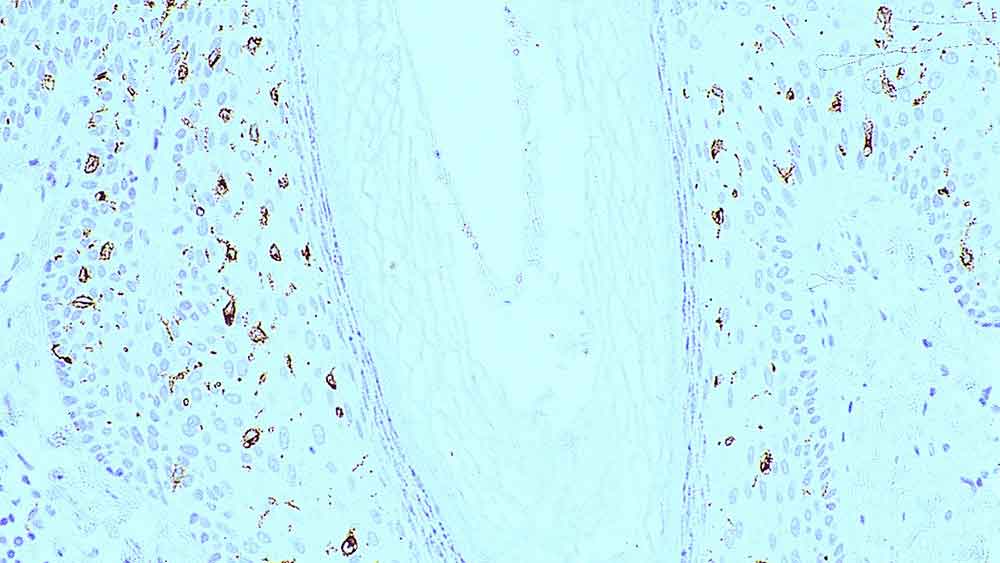

LANGERIN-L-U

1ml NCL-L-LANGERIN

LANGERIN-L-CE